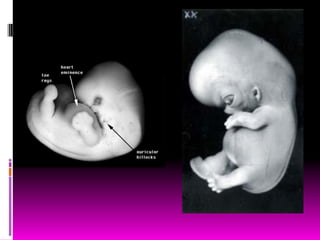

Cuarta semana

 Mide 2 ª 3.5mm de largo.

 Es casi recto

 Tiene 4 a 12 somitas

 Se forma el tubo neural

entre somitas opuestas.

 24días

 Son visibles los arcos

faríngeos (branquiales)

 Primer arco branquial o

mandibular

 Es más curvo

 El corazón bombea sangre

 26días

 Tres pares de arcos

branquiales o faríngeos,

cierre del neuroporo rostral.

 Cerebro anterior produce

elevación notable de la

cabeza, forma en C.

• Note:

• The future mouth and facial bones are already in position.

• Label Key:

• 1. 1st pharyngeal arch (maxillary process)

• 2. midbrain

• 3. 1st pharyngeal arch (mandibular process)

• 4. placental vessel

• 5. forebrain

• 6. chest wall

• 7. area of stomodeum (future mouth)

• 8. heart

• 9. 2nd pharyngeal arch

4ta semana